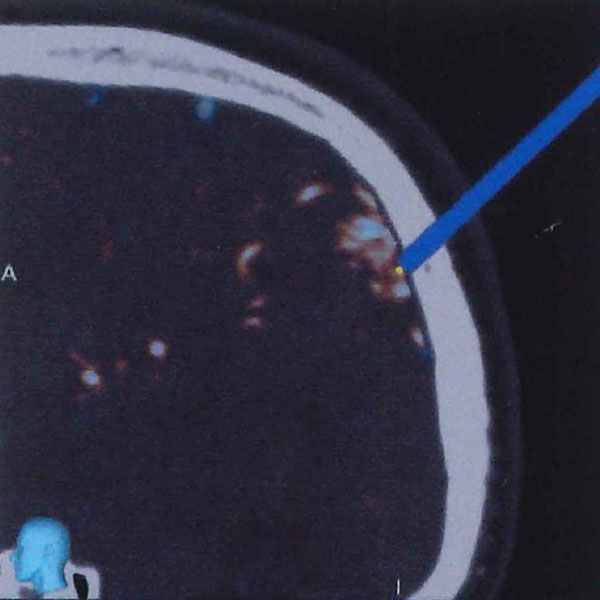

脳血管撮影

手術前

手術後

手術中

モニタリング

手術写真

手術の結果